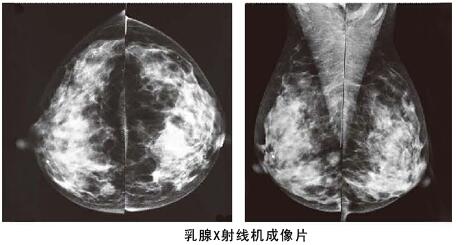

其實(shí)相比乳腺彩超,利用數(shù)字化鉬靶乳腺機(jī)對(duì)于乳腺管較細(xì)或者乳腺本身存在問題,可以進(jìn)行更加細(xì)致檢查,而且它是女性乳腺癌早期診斷的金標(biāo)準(zhǔn),數(shù)字化鉬靶乳腺機(jī)可以發(fā)現(xiàn)0.1毫米的鈣化點(diǎn),提示癌前病變。是各種乳腺疾病檢查的必備醫(yī)療設(shè)備:如乳腺炎癥,乳腺增生,乳腺纖維瘤,乳腺囊腫等。對(duì)于一些年齡較大的女性來說,數(shù)字化鉬靶乳腺比乳腺彩超檢查更加的準(zhǔn)確。